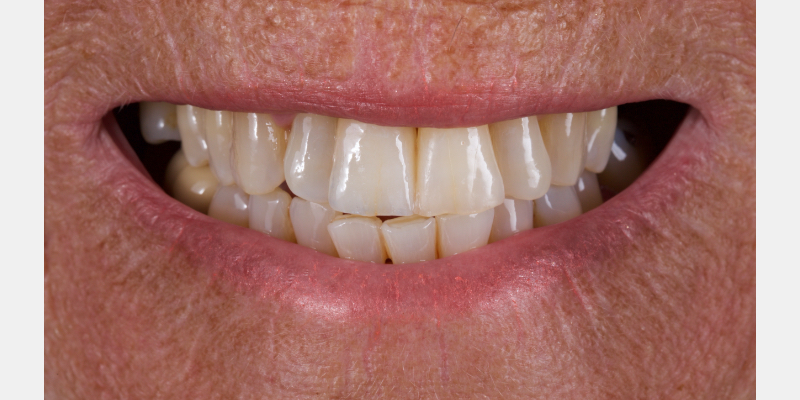

Take Arthur, a 76-year-old man who presented with a vertical root fracture of his upper left central incisor. His medical conditions precluded his request for an implant, so he agreed to the proposal for an adhesive bridge instead.

The tooth was extracted and for four months the pontic site was conditioned with a removable Essix-type of denture (Fig. 1).

An e.max (lithium disilicate), one-wing (adjacent central being the retainer) bridge was placed, which resulted in an acceptable outcome (Figs. 2-4) that was more timely and at a lower financial and biological cost to the patient than the implant Arthur initially thought he wanted.